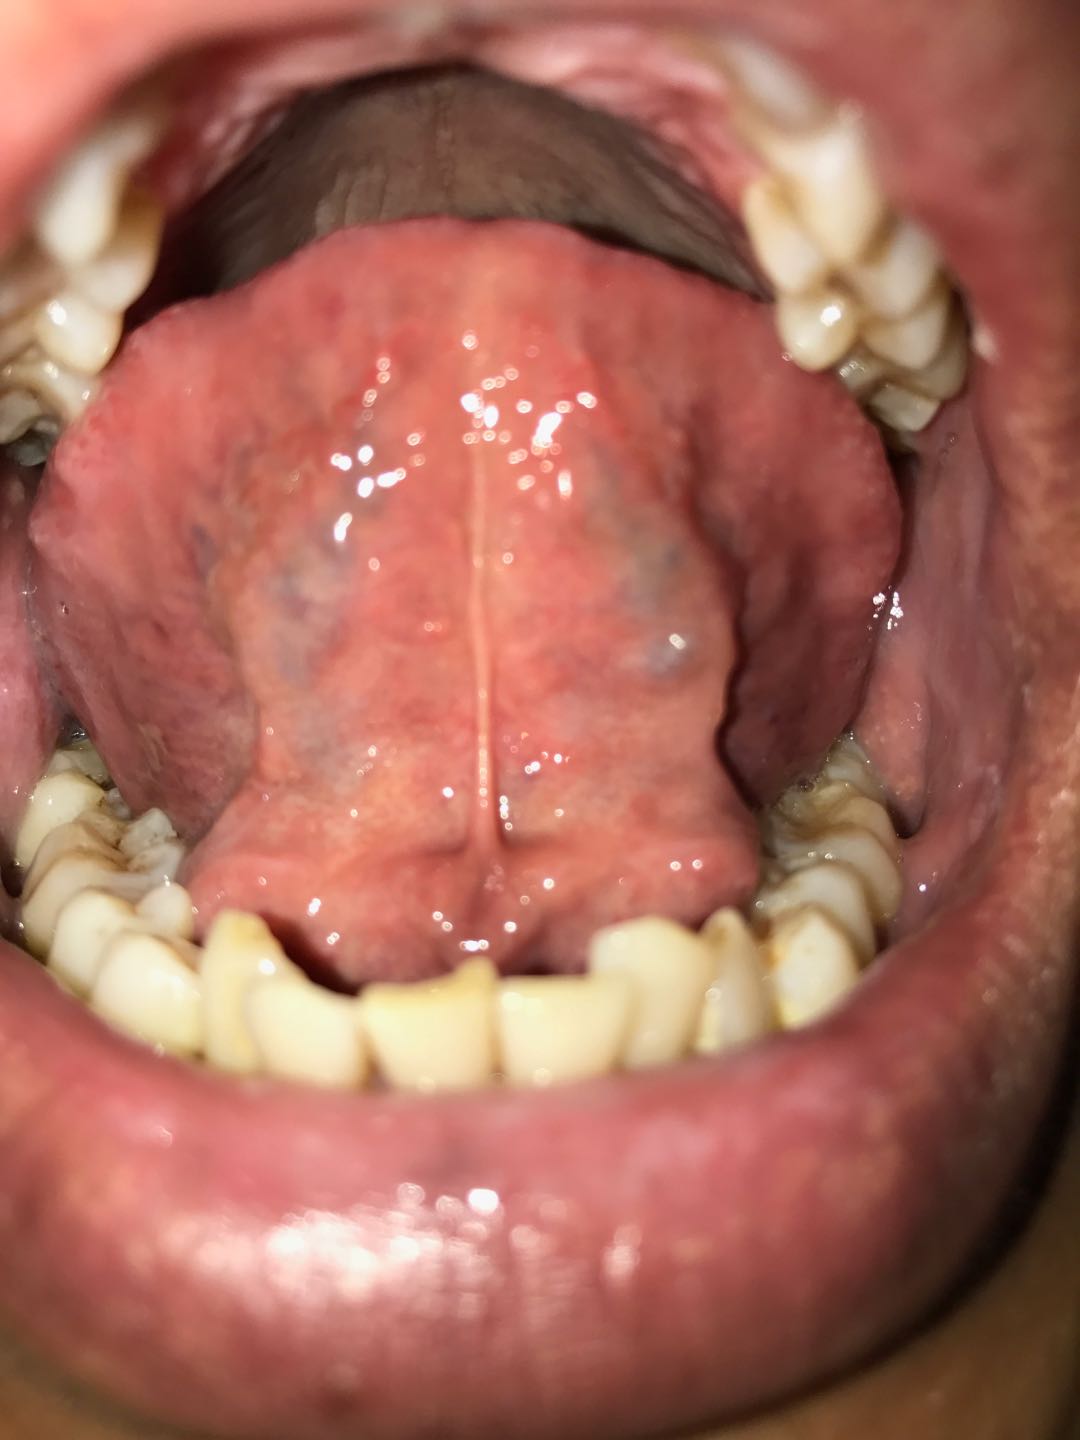

5、舌苔还是黄厚腻;

由于昨天脸又热了一天,所以昨晚就没熬药了,请问老师我这种情况是否还继续喝药,不吝赐教,谢谢。另附今早舌照两张。

虽然大便成行,颜色黄,不粘马桶,但从第一张舌照上看,根苔黄厚腻,加上小便黄,有泡沫,不易消散,脸又有点热了,下焦湿热还是较重。

3、舌苔还是黄厚腻,详见下图,今早起的舌照;

老师,您好!今天最后一天药吃完了,昨晚散步时惊喜的发现会发屁了,还连着好几个,从昨下午始小便不那么黄了,但泡沫还是丰富的,别的情况和昨天描述的一样。老师您看我是接着吃这个药呢还是您再开过别的药,请不吝赐教,期盼您的回复,谢谢!另附今早舌照。

4、舌苔还是黄厚腻,详见下图,今早起的舌照;

老师,以上就是这段时间的基本情况,请您参考辨证,接下去您看该如何继续调理,请老师您不吝赐教,谢谢!另附三张今早舌照。